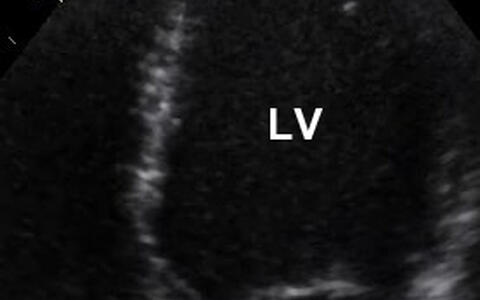

In a healthy heart, the left ventricle, LV (above right), the right ventricle (above left), and their atriums are surrounded by compact muscle tissue. (Picture: Sabine Klaassen/​Copyright: MDC)